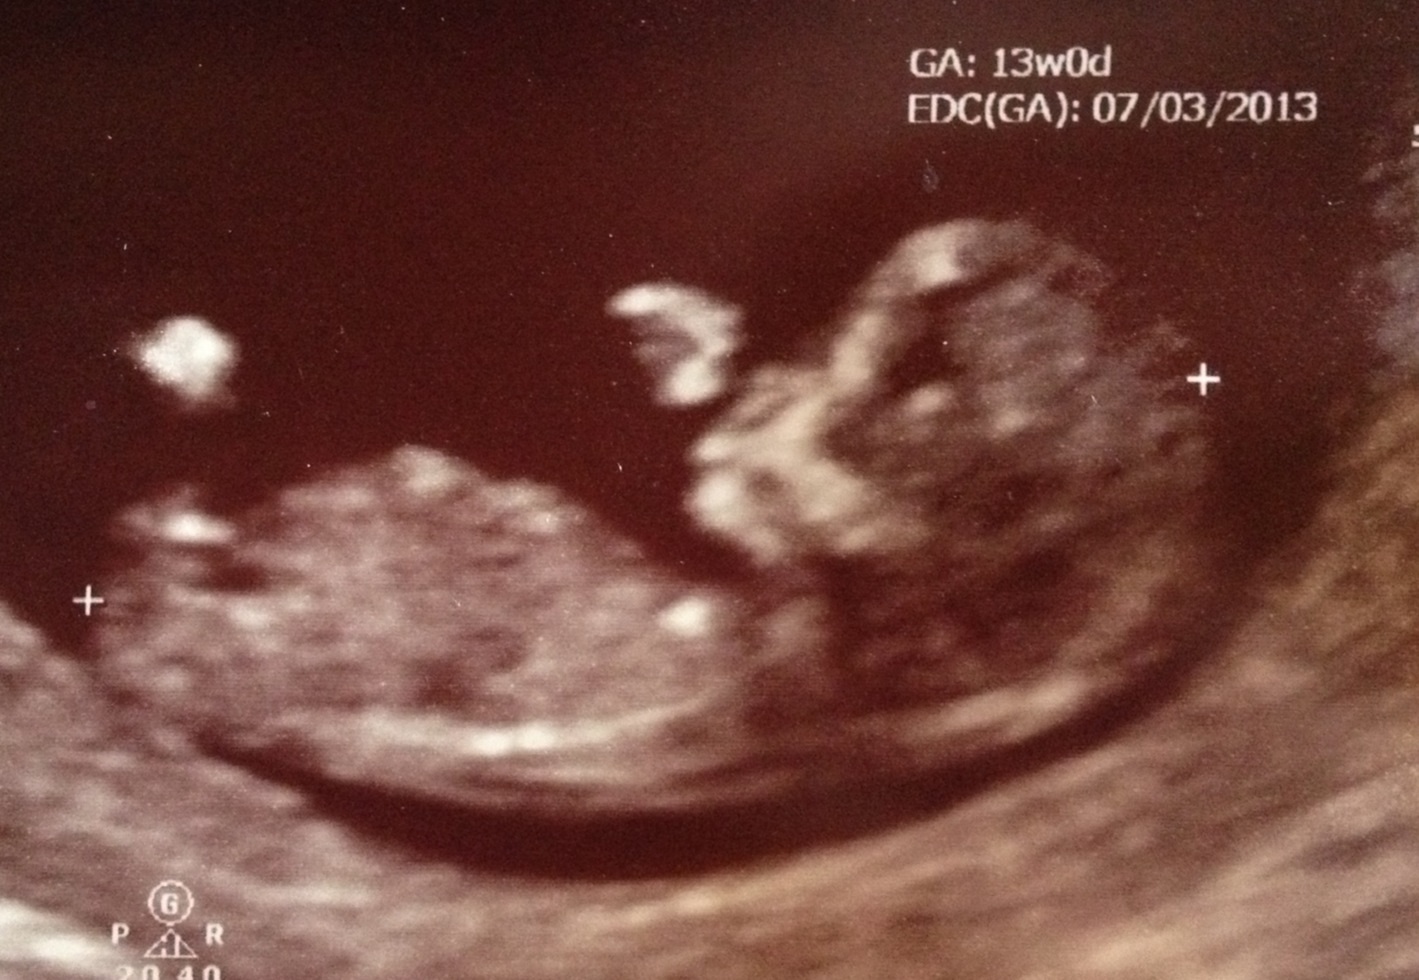

Here is my 13 week sonogram pic. Baby measured 12 weeks 3 days. Tech guessed 80% girl. Do you agree? Attachment 8415

It's a girl!!!! (Confirmed at 18 weeks)